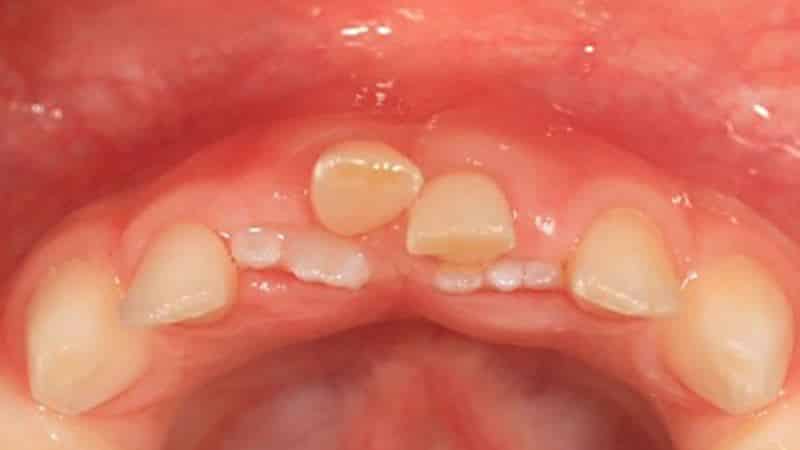

Существуют случаи, когда молочные зубы не выпадают, а коренные уже начинают расти. В таких ситуациях у детей часто возникают боли и дискомфорт в ротовой полости, что требует консультации стоматолога. Обращение к специалисту в таких случаях может предотвратить искривление и неправильный рост новых зубов.

Возможно, потребуется лечение, так как могут возникнуть воспалительные процессы или осложнения. Неправильный рост зубов также может стать проблемой, что в дальнейшем приведет к неправильному прикусу.